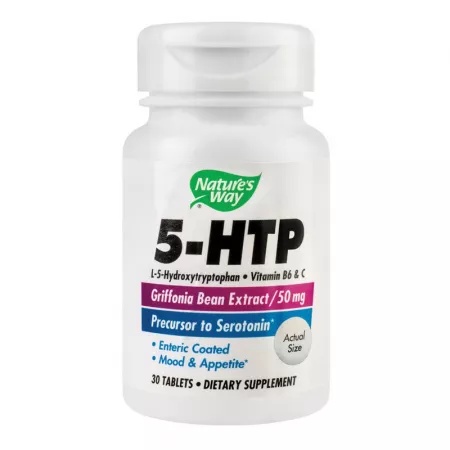

184,82 lei5-HTP Nature’s Way, 30 tablete, Secom